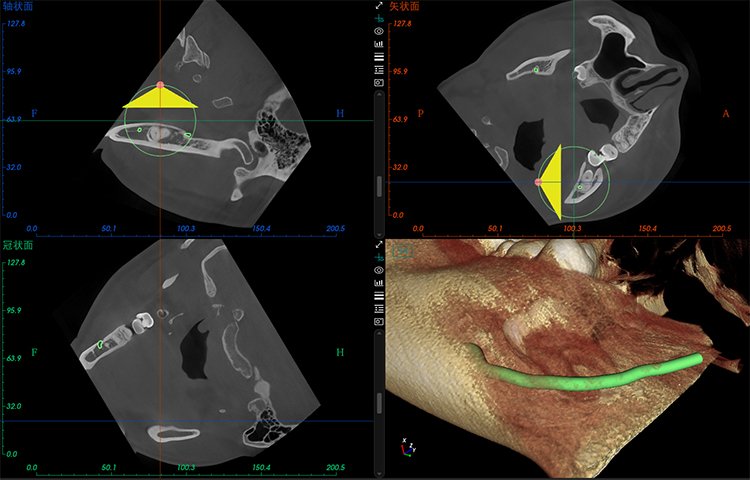

El software de diagnóstico 3D líder de Meyer y el sistema de análisis ortodóntico inteligente adoptan un diseño de UI modular, lo que hace que las funciones del software sean más cercanas a las necesidades clínicas y más fáciles de usar para los médicos, reduciendo significativamente el costo de aprendizaje.

Software de Diagnóstico 3D

MyDentViewer